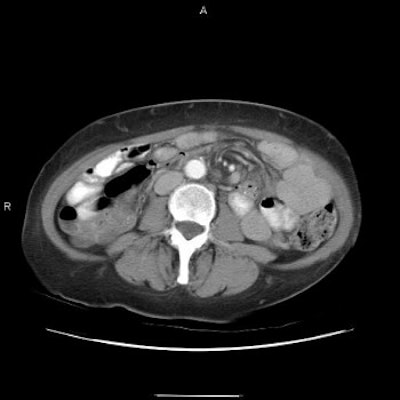

Both UGI and CT detect signs signaling adhesion or internal hernia, such as dilated bowel segments and a transition from dilated to collapsed bowel. But only CT depicts classic signs of internal hernia such as crowding, stretching, and engorgement of mesenteric vessels.

Three images show internal hernia following Roux-en-Y gastric bypass. The CT scans (top, middle) and small bowel study (below) show a cluster of mildly dilated bowel segments in the left abdomen, with a crowded, twisted appearance of the bowel and mesenteric vessels. Images courtesy of Dr. Michael Federle.